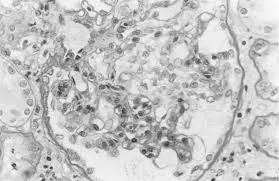

Injúria Renal Aguda (revisão Lancet 2025)